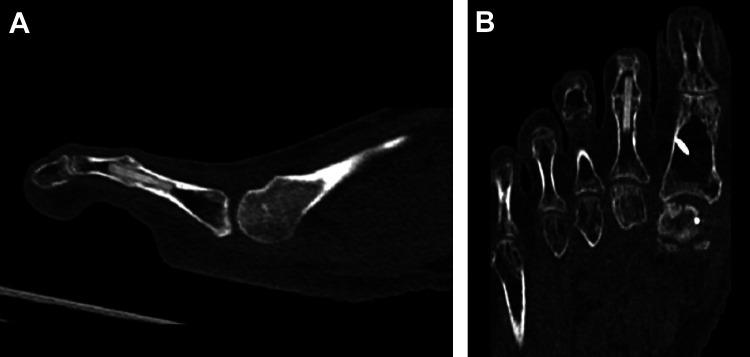

A novel biointegrative implant was developed for proximal interphalangeal joint (PIPJ) arthrodesis to treat hammertoe deformity. Composed of continuous reinforcing mineral fibers bound by bioabsorbable polymer matrix, the implant demonstrated quiescent, gradual degradation with complete elimination at 104 weeks in animal models. This prospective trial assessed the implant's safety, clinical performance, and fusion rate of PIPJ arthrodesis for hammertoe correction.

Twenty-five patients (mean age 63.9±7.5 years) who required PIPJ arthrodesis were enrolled at 3 centers. Outcomes included radiographic joint fusion, adverse events, pain visual analog scale (VAS) score, Foot and Ankle Ability Measure (FAAM) Activities of Daily Living (ADL) score, and patient satisfaction. Patients were evaluated 2, 4, 6, 12, and 26 weeks postoperatively.

Twenty-two patients (88%) achieved radiographic fusion at 26 weeks. All joints (100%) were considered clinically stable, with no complications or serious adverse events. Pain VAS improved from 5.3±2.5 preoperatively to 0.5±1.4 at 26 weeks postoperatively. FAAM-ADL total scores and level of functioning improved by mean 19.5±19.0 points and 24.4±15.7 percentage points, respectively, from preoperation to 26 weeks postoperation. Improvements in pain VAS and FAAM scores surpassed established minimal clinically important differences. All patients were very satisfied (84%) or satisfied (16%) with the surgery. Patient-reported postoperative results greatly exceeded (72%), exceeded (20%), or matched (8%) expectations.

This prospective, multicenter, first-in-human clinical trial of a novel biointegrative fiber-reinforced implant in PIPJ arthrodesis of hammertoe deformity demonstrated a favorable rate of radiographic fusion at 12 and 26 weeks, with no complications and good patient-reported clinical outcomes.